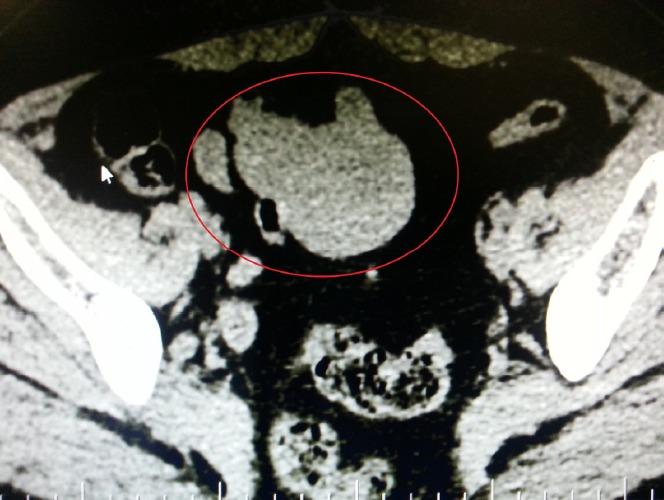

Gastrointestinal stromal tumors (GISTs) are rare tumor of the gastrointestinal tract. GISTs occur in the entire gastrointestinal tract and may also arise from the retroperitoneum, omentum and mesenteries. They are originated from gastrointestinal pacemaker cells (Cajal's interstitial cells) and range from benign tumors to sarcomas at all sites of occurrence. Diagnosis of GIST could be deceptive because of their similarity in appearance to gynecological neoplasms. We would like to present a case of a woman with GIST in the small intestine giving a imprint of an adnexal mass was diagnosed correctly during surgery. The diagnosis and treatment of GIST has been reformed over the past years. It is crucial to separate GISTs from possible misdiagnosis because their prognosis and treatment could be unlike clearly. The purpose of this case is to evaluate this rarely seen clinical entity, and thus, make some contribution to the literature.

胃肠道间质瘤(GISTs)是胃肠道的罕见肿瘤。GISTs可发生于整个胃肠道,也可能起源于腹膜后、网膜和肠系膜。它们起源于胃肠道起搏细胞(卡哈尔间质细胞),在所有发生部位的肿瘤性质从良性到肉瘤不等。由于GISTs外观与妇科肿瘤相似,其诊断可能具有欺骗性。我们在此呈现一例小肠GISTs患者的病例,该患者在手术中被正确诊断,其表现曾被误诊为附件肿物。在过去几年中,GISTs的诊断和治疗方法已经有所革新。将GISTs与可能的误诊区分开来至关重要,因为它们的预后和治疗方法可能有明显不同。本病例的目的是评估这种罕见的临床实体,从而为相关文献做出一些贡献。